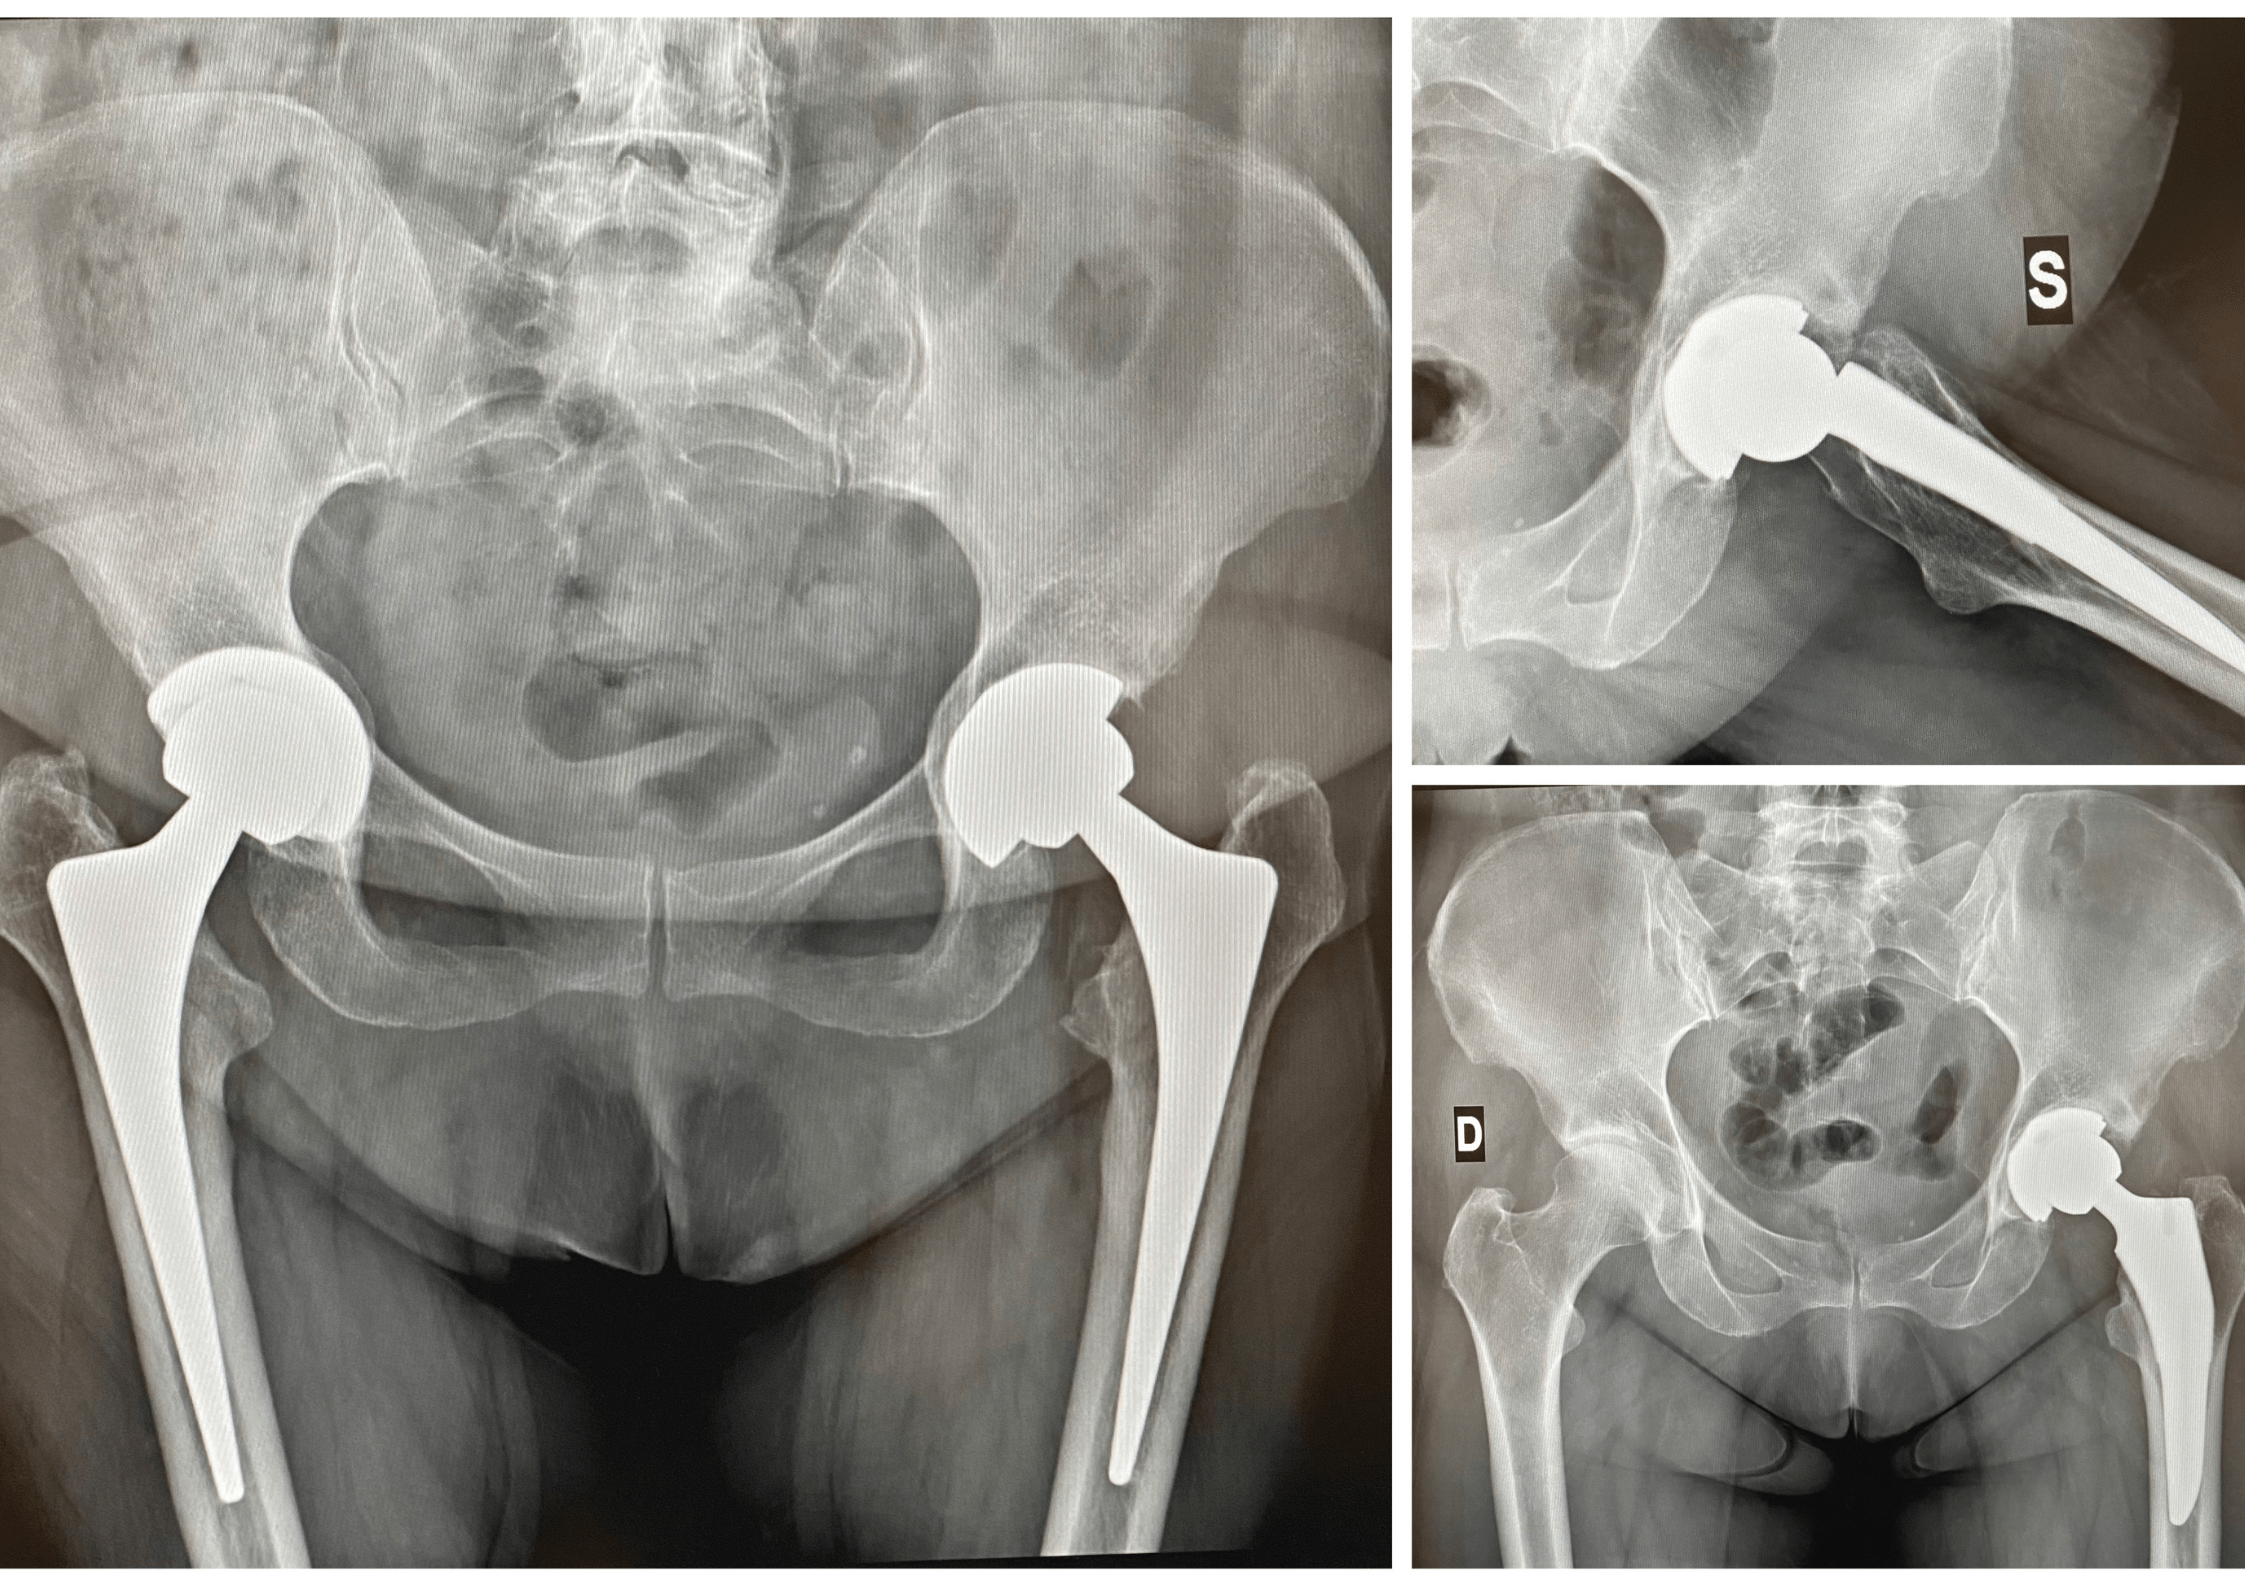

A cosa serve la radiografia del bacino per l'anca?

La radiografia del bacino per l'anca è utilizzata principalmente per diagnosticare e valutare condizioni come fratture, artrite, displasia dell'anca, necrosi avascolare, tumori ossei e altre patologie che possono interessare l'anca e il bacino

Questo esame è utile anche per monitorare la guarigione di fratture, valutare l'efficacia di trattamenti ortopedici e pianificare interventi chirurgici.

La radiografia del bacino per l'anca fornisce immagini dettagliate che aiutano i medici a fare una diagnosi accurata e a decidere il trattamento più appropriato.